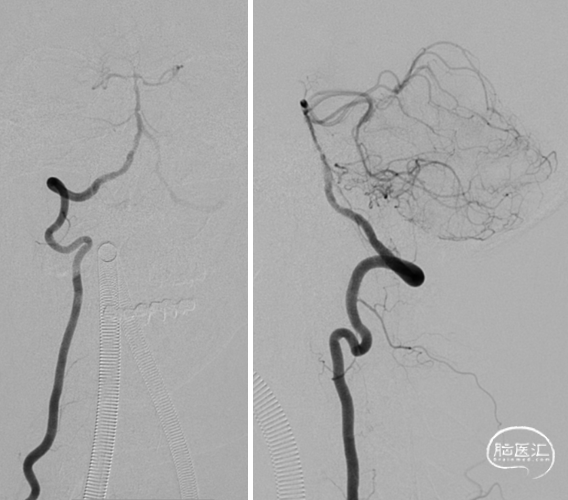

6F 90cm 长鞘+5F 115cm 通桥银蛇®颅内支持导管建立通路。

0.014in*200cm 微导丝超选,球扩支架 2.5*8mm到位。

充盈球囊支架释放。

术后造影:基底动脉狭窄消失,双侧AICA通畅。